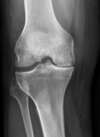

• Radiologique : le cartilage n'étant pas visible à la radiologie, il existe normalement un espace entre les deux os qui se regardent au niveau de l'articulation. Quand l'arthrose évolue, le cartilage disparaissant, cet espace diminue et au maximum les os se touchent (pincement articulaire radiologique)

radiographie du genou : arthrose visible grâce au "pincement articulaire" entre fémur (en haut) et tibia (en bas), avec ostéophytes ("becs de Perroquet")